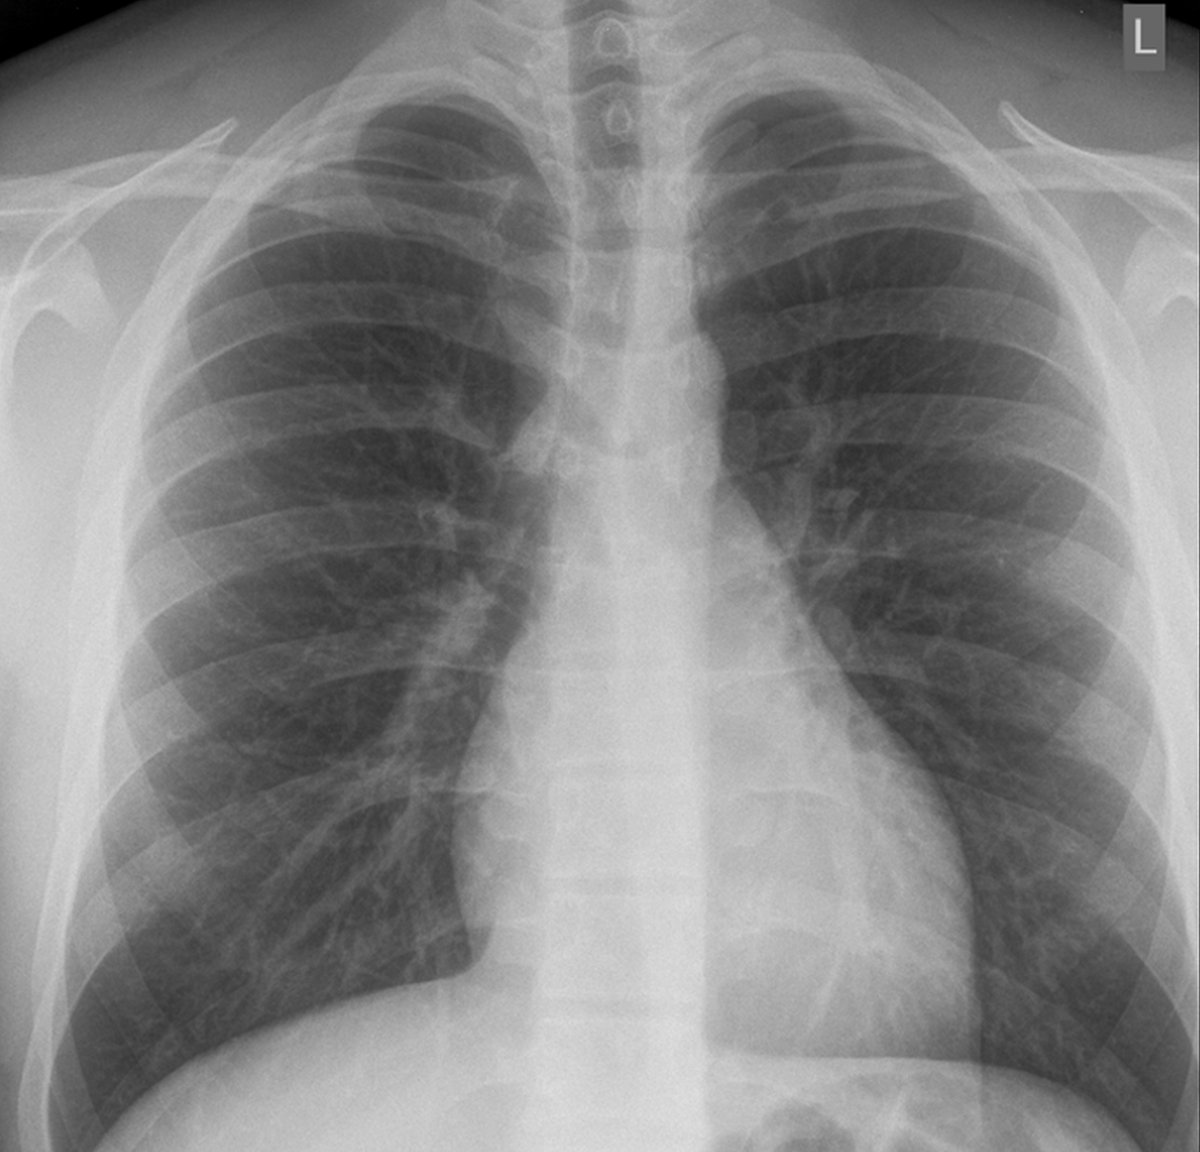

У 20-летнего мужчины возникла боль в горле и сухой кашель, которые сопровождались лихорадкой и одышкой в течение четырех дней. В день поступления в стационар у пациента не было признаков нарастания дыхательной недостаточности. Исходное насыщение крови кислородом при самостоятельном дыхании в помещении отделения неотложной помощи составило 95 %. Лабораторные анализы показали отсутствие значительного повышения ключевых показателей. Согласно больничному протоколу, была сделана базовая рентгенография грудной клетки и дополнительное УЗИ легких. Рентгенография грудной клетки не показала типичных признаков пневмонии COVID-19 (рис. 1).

Рис. 1. На исходной рентгенограмме грудной клетки нет снижения прозрачности; типичных признаков пневмонии COVID-19 не обнаружено.